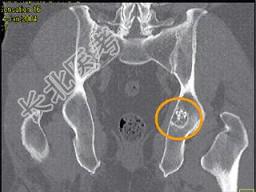

- 单项选择题患者40岁,男性, 如图所示,最可能的诊断是 ( )

A、骨样骨瘤

B、转移瘤

C、内生软骨瘤

D、软骨肉瘤

E、以上都不是